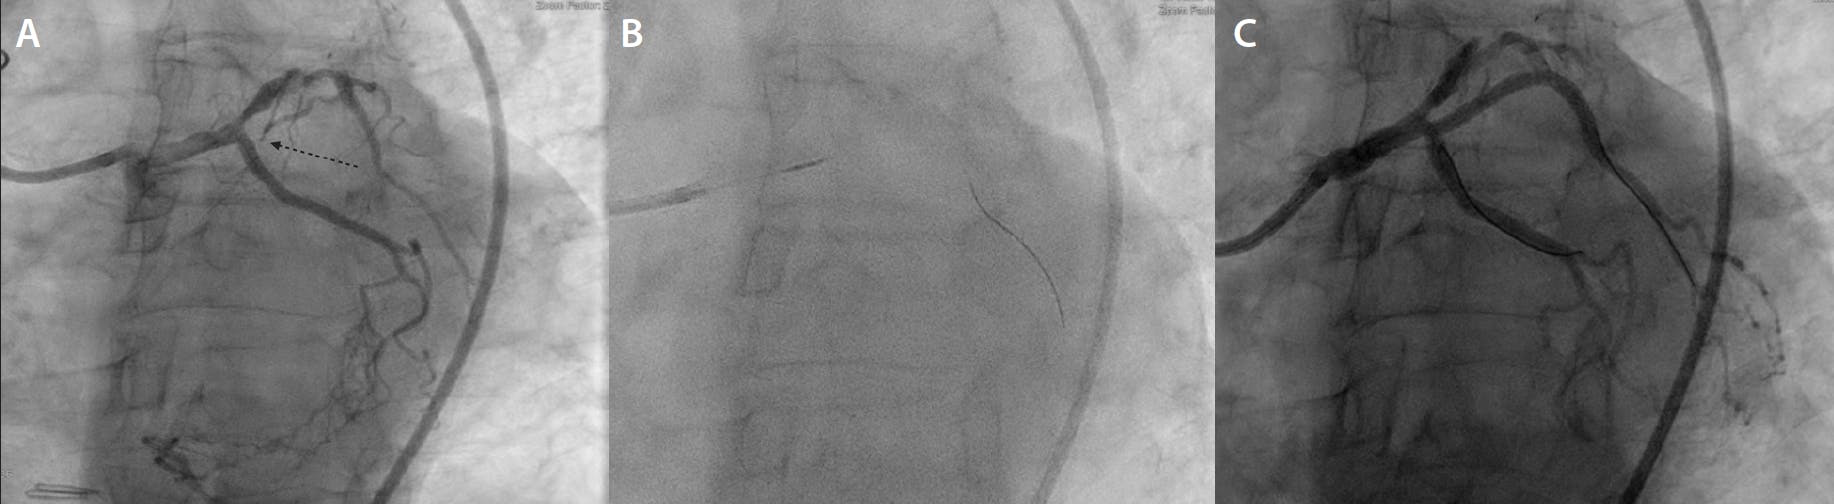

A man in his early 60s with a history of hypertension, hyperlipidemia, current tobacco use, and prior coronary artery bypass grafting (CABG) (left internal mammary artery [LIMA]–left anterior descending artery [LAD], saphenous vein graft [SVG]–ramus artery), presented to an outside hospital with intermittent chest pain lasting 1 week. In the emergency department, an electrocardiogram showed lateral ST depression and an elevated high-sensitivity cardiac troponin of 900 ng/L, which peaked at 1,900 ng/L. Transthoracic echocardiography showed preserved left ventricular ejection fraction (LVEF) with anterolateral akinesis. Coronary angiography demonstrated an occluded SVG-to-ramus, patent LIMA-to-LAD, and severe native triple-vessel disease, including subtotal occlusion of the native ostial ramus (arrow) (Figure 1A). No percutaneous intervention was performed at the outside hospital. He was managed medically with heparin infusion for 48 hours and discharged on dual antiplatelet therapy with aspirin and clopidogrel. At follow-up with his primary cardiologist, the patient continued to report recurrent angina despite maximally tolerated medical therapy. He was subsequently referred to our center for evaluation and consideration of native ramus revascularization. After discussing the risks and benefits of the procedure, we decided to proceed with PCI.

Figure 1. Coronary angiography demonstrating an occluded SVG-to-ramus, patent LIMA-to-LAD, and severe native triple-vessel disease, including subtotal occlusion of the native ostial ramus (arrow) (A). The ostial ramus subtotal occlusion was successfully wired (B). A drug-eluting stent was deployed and postdilated, yielding an excellent result with no complications (C).

The right common femoral artery was accessed using a micropuncture kit under ultrasound guidance. A 7-F Pinnacle® sheath (Terumo Interventional Systems) was inserted over a 0.035-inch wire. A 7-F EBU 3.5 guiding catheter (Medtronic) was seated in the left main coronary artery. Using a Runthrough NS Izanai coronary wire loaded in a Turnpike™ LP microcatheter (Teleflex), the ostial ramus subtotal occlusion was successfully wired (Figure 1B). Luminal positioning was confirmed, followed by serial balloon dilations. A 2.5- X 33-mm Xience Skypoint™ drug-eluting stent (Abbott) was deployed and postdilated with a 3-mm NC balloon, with an excellent result and no complications (Figure 1C).